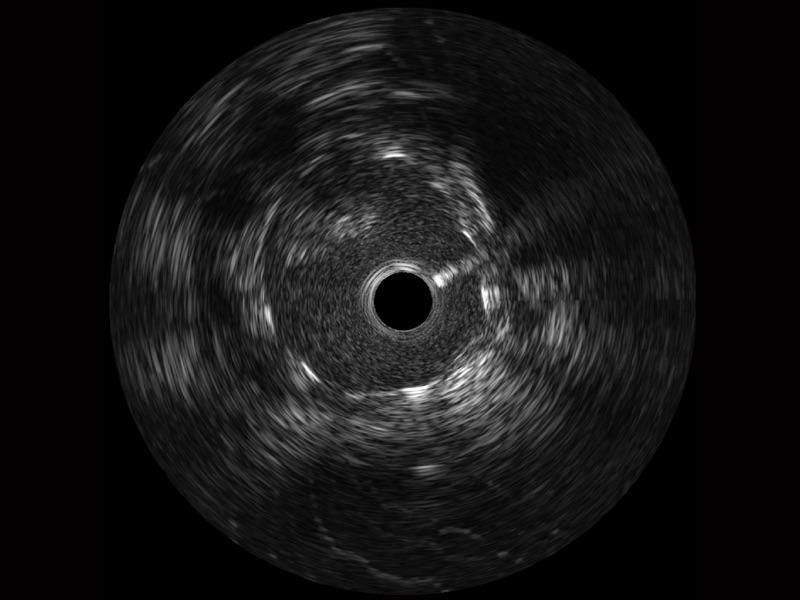

米兰官方网站宽频IVUS图像

对比传统IVUS导管成像,米兰官方网站宽频IVUS图像的近场支架梁显影更细腻,远场中膜外血管仍清晰可辨,兼顾远中近,兼顾分辨力与穿透深度